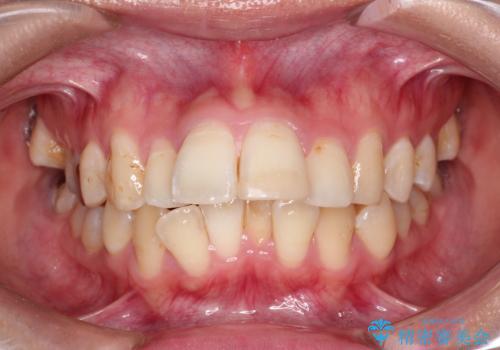

- 前歯の凸凹を主訴に来院されました。

前歯を並べるために歯と歯の間にヤスリを入れてわずかに歯を削ることでスペースを確保しています。